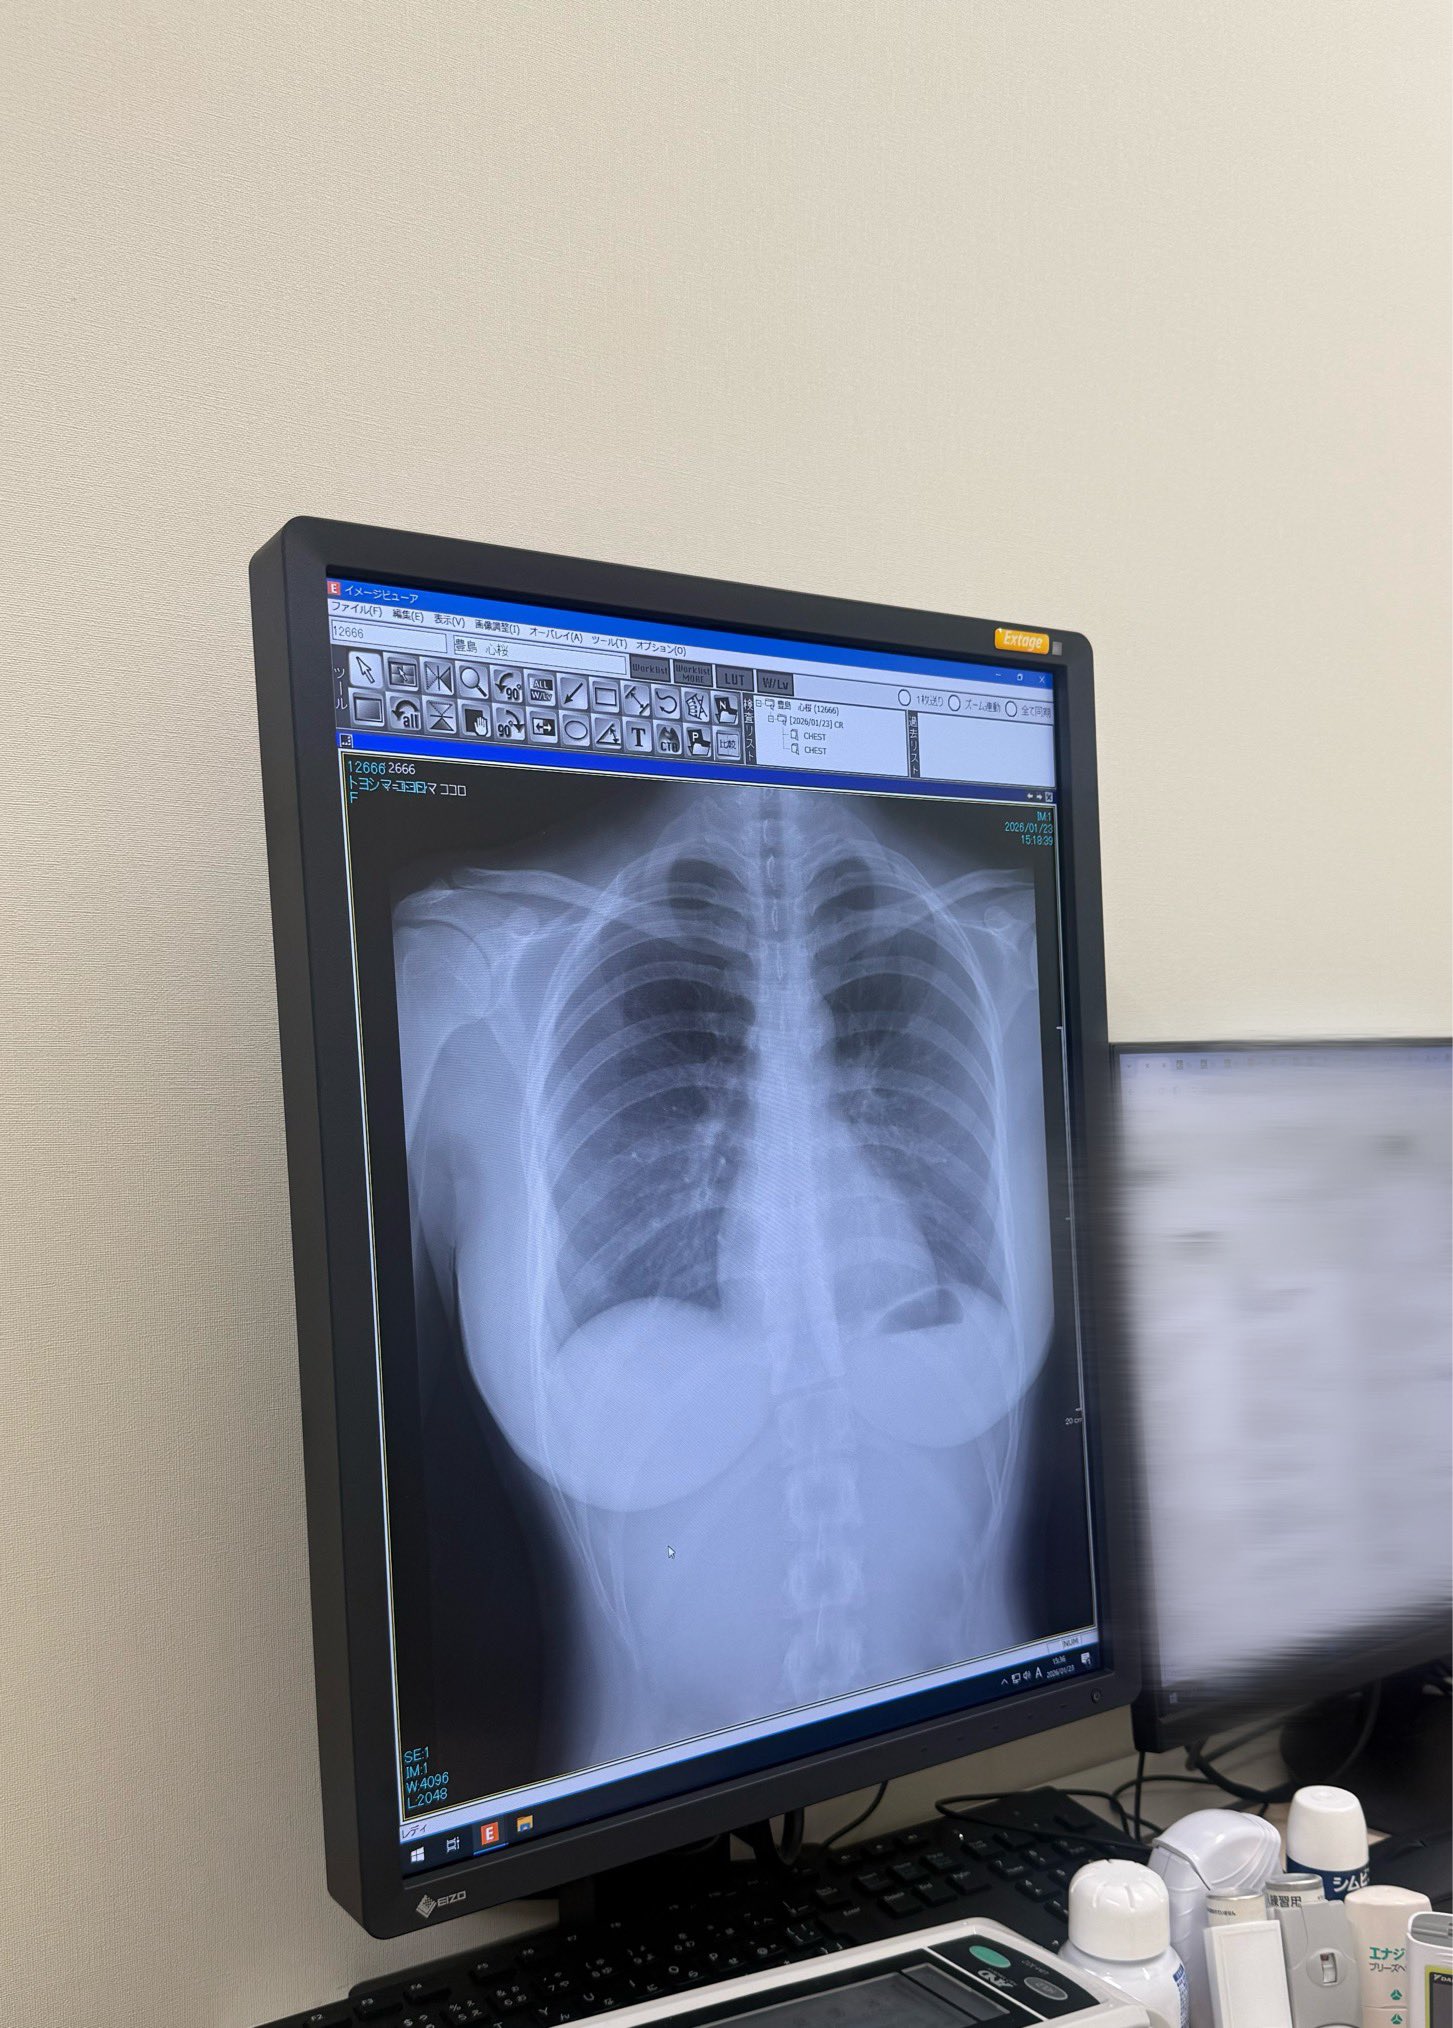

爆乳はレントゲンにも映るんだな

豊島 心桜(こころ)さんのスケスケおっぱい

名前映っとる!

レントゲンに映ってる肩関節や背骨の突起や肋骨の立体的な構造がこんな綺麗な人の身体に収まってるの感動する

肋骨が美しく見える気がする

くびれの形になってるんだな

シリコンはばっちり像影されるけど最近主流の豊胸は脂肪注入だからレントゲンでもわからないってプロがこれに淫リツしてた

進化してるんだなオッパイも

レントゲンよく見ると背骨ってまっすぐじゃなくてゆるくS字になってるんだな

側面から見るとそうだが正面からはまっすぐなのが普通だぞ

加齢とか生まれつきとかで左右にS字になる人もまあまあ居るけど程度が酷ければ脊柱側弯症という病気になる

スレ画くらいなら異常ってほどではないし何も問題はないけどお婆さんになった時にはもっと曲がってるかもな